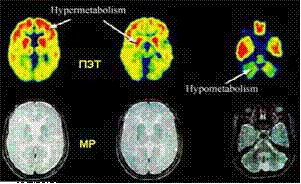

- исследование метаболизма тканей

головного мозга

Рисунок 17 - Исследование метаболизма головного

мозга

- дагностика эпилептогенных фокусов

методик затруднительно.[13] ПЭТ с фторглюкозой позволяет оценить увеличение или

уменьшение потребления глюкозы и локализовать эпилептогенные фокусы.